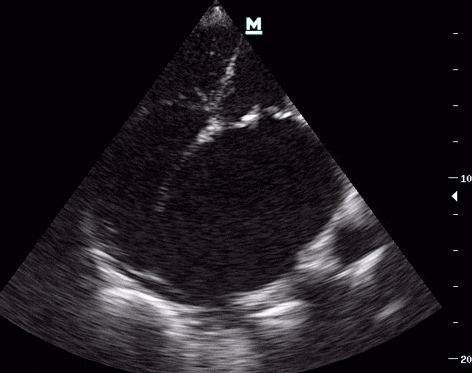

85 yaşında bir kadın hastada acil ultrasonografi görüntülemesi sırasında alınan EKO görüntüleri.

1. Biatriyal genişleme, özellikle sol atriyumda (Figür 1).

2. Kalsifik mitral kapak ve kısıtlı kapak açılımı (Figür 1).

4. Mitral kapak posteriorda immobil hiperekojen (kalsifik) kitle görünümü (Figür 3-4).

Mitral annulus kalsifikasyonu ve posterior mitral kapakta kalsifiye kitle birlikteliği literatürde sıklıkla yaşlı ve diyaliz hastalarında daha sıklıkla gösterilmiştir. Kitle saptanan hastalarda tromboemboli riski ve kitle ayırıcı tanısı için sıklıkla cerrahi gerekir. Ayırıcı tanılar arasında kalsifiye kardiyak miksoma, fibroma, fibroelastoma ve kazeöz mitral anuler kalsifikasyon yer alır.3

Görüntüler bu hastada mitral kapakta kitle patolojisine sekonder mitral stenoz ve regurjitasyon gelişmesini ve sonrasında da dev sol atriyum meydana gelmesini işaret etmektedir. Burada yazılmayan sizin gözünüze çarpan başka tanıları yazımızın altında belirtebilirsiniz.